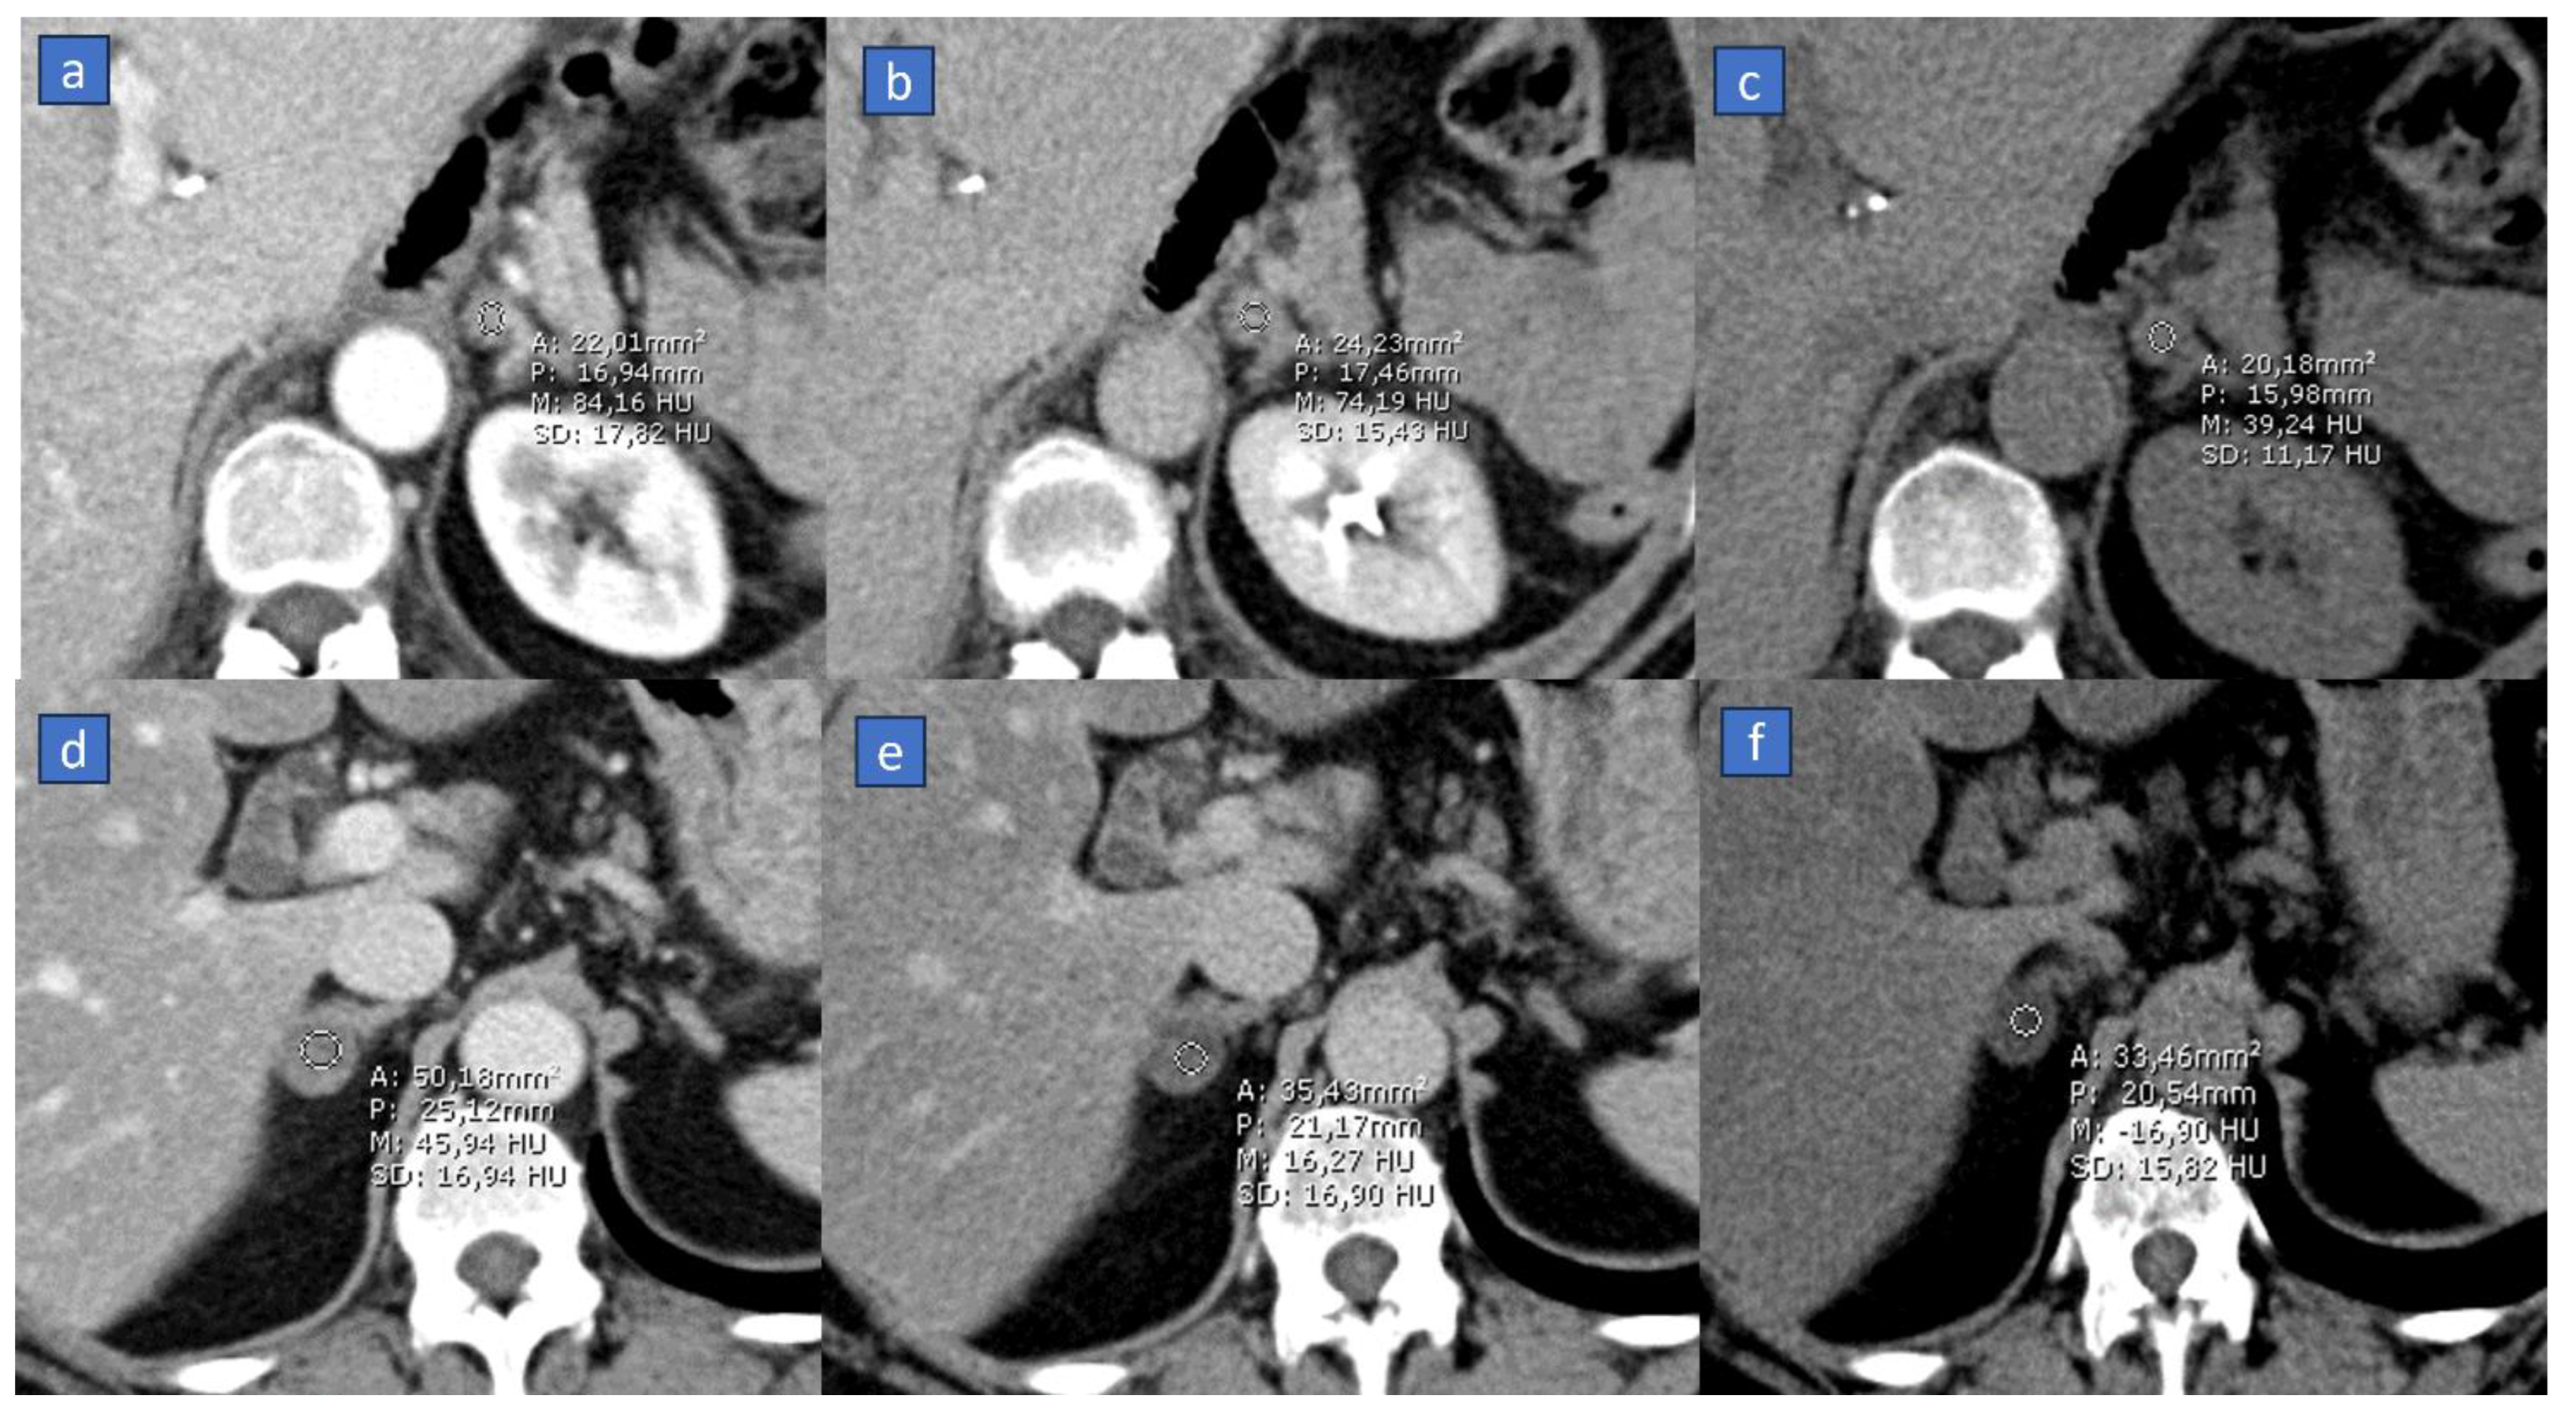

2. Virtual Non-Contrast (VNC)

Applications